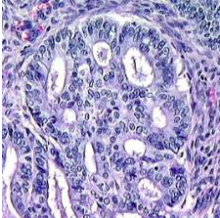

neoplasm

hypercellular compared to the tissue normally seen in that site. Since increased nuclear to cytoplasmic ratio is a characteristic of malignant cells, most malignancies appear as a very blue lesion on H and E.